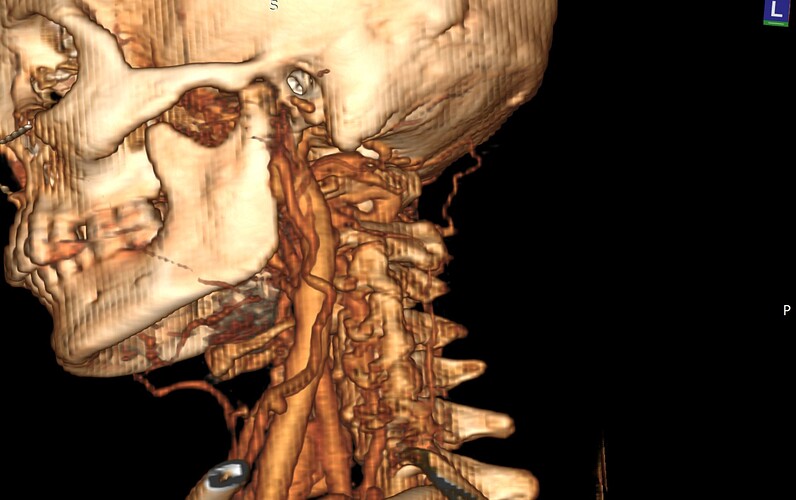

@chrEagle really hard to draw any strong conclusions from the 3D models. The best view is the axial view.

I can’t see your styloids at all on those images, nor the C1 processes, so can’t comment, the IJVs look fairly full but it can look very different on the axial views as @TML says. I would say though that your neck looks like it’s lost it’s natural curve- aka military neck- which we see quite often. This could be contributing to a forward head posture which may make symptoms worse, or it could be it’s your body’s way of trying to open up the space in your neck, it’s one of those dilemmas we don’t know the answer too! But there are exercises which you could try in this post:

@chrEagle see attached annoted images (5 here of the axial view, and a 3D model in a following post)

You can actually see the tortuous left ICA run into the left IJV in the 3D model I posted:

@chrEagle I re-downloaded your CT to get better 3D images of the compression in question.

See attached. Hope this helps!